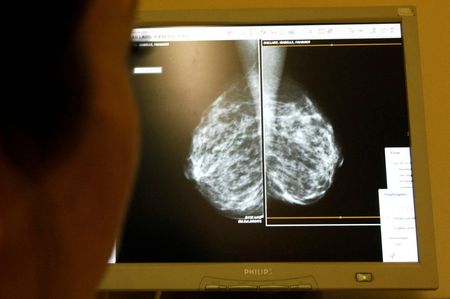

NEW YORK (Reuters) -Women at average risk for breast cancer should get screening mammograms every other year starting at age 40, the U.S. Preventive Services Task Force (USPSTF) said on Tuesday, cementing insurance coverage for the procedure for that age group under the law.

The USPSTF’s influential recommendation, published in JAMA, reverses its controversial 2009 guidance that breast cancer screening should begin at age 50.

Its updated guidelines bring it in line with other major organizations that say women at average risk of breast cancer should start screening at age 40.

By lowering the age to start biennial screening to 40, the USPSTF is acknowledging evidence that more women under the age of 50 are now getting diagnosed with breast cancer.